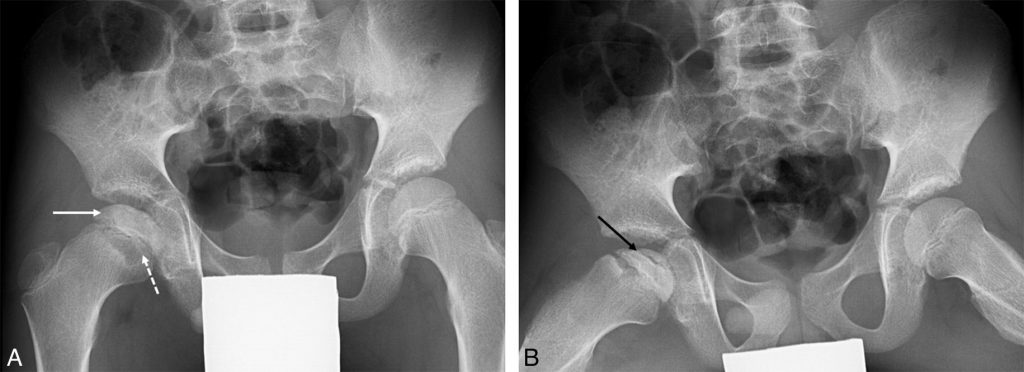

La radiographie est normale au début de la maladie puis la nécrose devient visible : liseré de dissection sous-chondrale, condensation de la tête, aplatissement de l’épiphyse (figure 114.2).

Fig. 114.2 Boiterie droite chez un enfant de 10 ans, sans fièvre.

La radiographie de bassin de face (A) montre une condensation et un aplatissement de l’épiphyse fémorale proximale droite (flèche). La métaphyse proximale est irrégulière (flèche en pointillé). Sur l’incidence de profil (B, incidence de Lauenstein), il existe un liseré de dissection sous-chondrale (flèche noire) témoignant de l’ostéonécrose.

Source : CERF, CNEBMN, 2022.